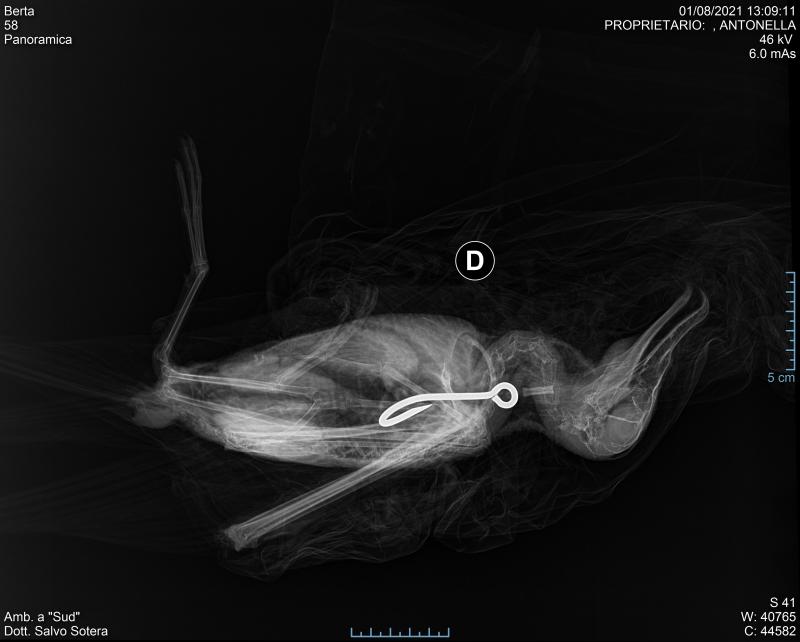

Berta maggiore che ha ingerito un amo

Berta maggiore che ha ingerito un amo © Archivio Lipu